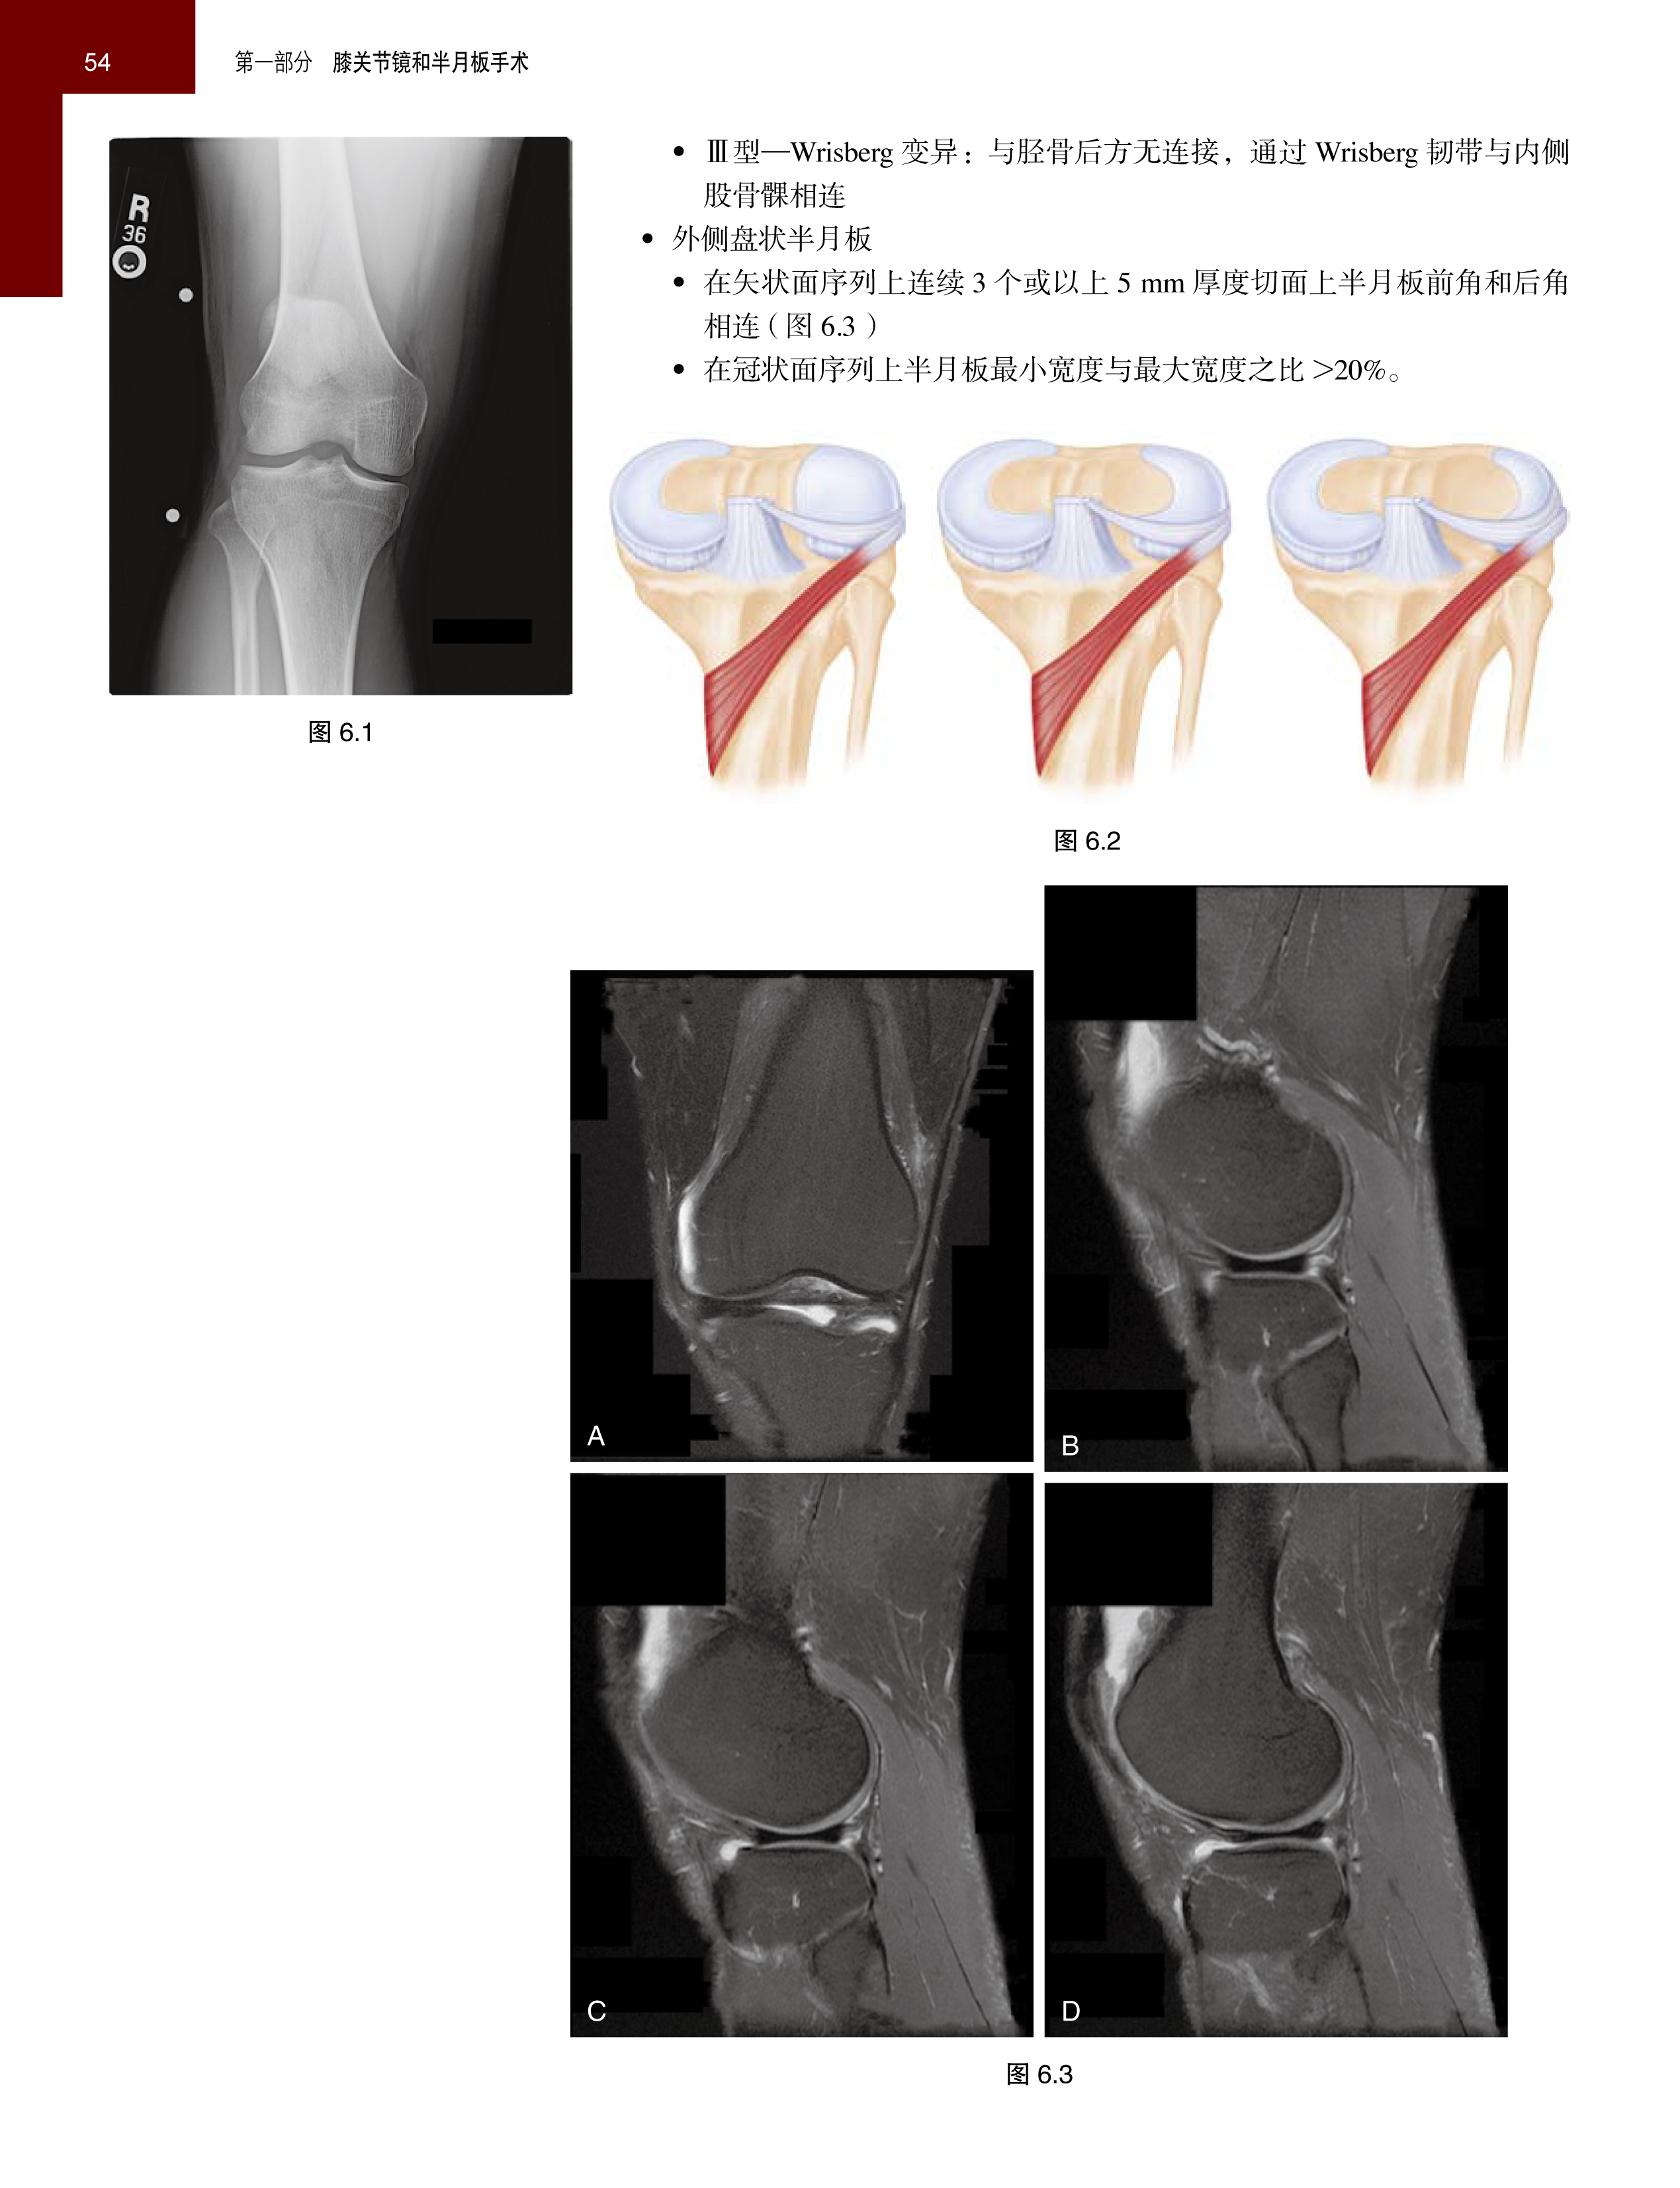

手术操作一目了然。手术的每一个操作都有清晰的手术图片,患者的病情和手术结果也都有放射影像图片。

介绍病例有如身临其境。书中配有大量彩色手术照片以及标出主要解剖结构的示意图。